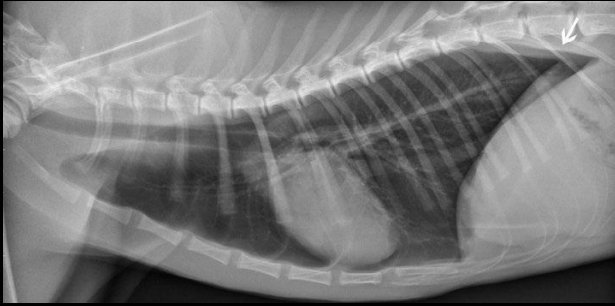

Anatomía del tórax en Rx

En una radiografia se ve:

- Silueta cardiaca

- Pulmones + Pleura

- Cavidad pleural

- Mediastino

IMPORTANTE. Siempre se toman las radiografias en el maximo insporatoria.